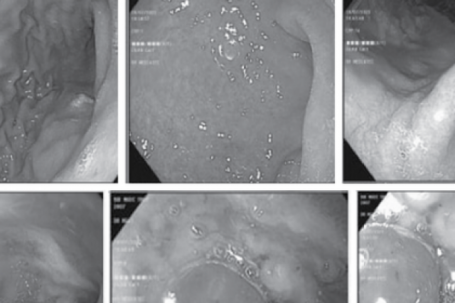

Dạ dày cồn cào, người phụ nữ phát hiện bệnh chưa từng có trên y văn tại Việt Nam

Bắt đầu từ các triệu chứng cồn cào trong dạ dày hay đau thượng vị, sau rất nhiều lần nội...